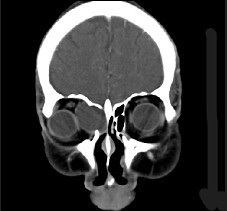

辅助检查中最有意义的发现是(如图)()